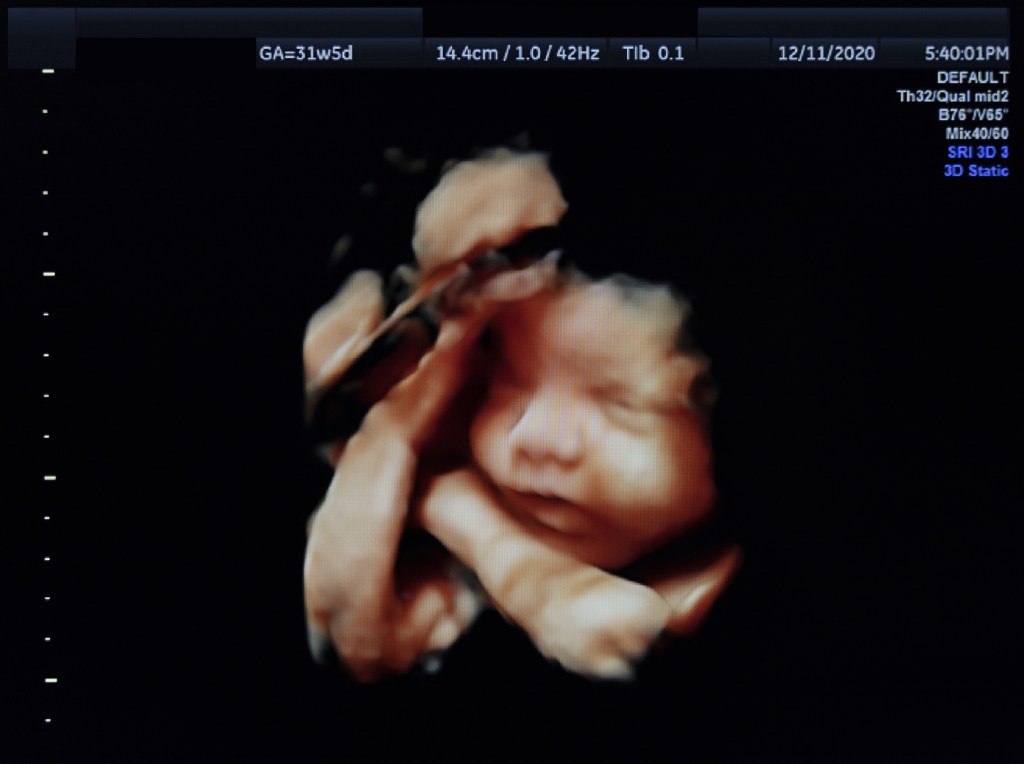

- Medición de la biometria del bebé. En estas semanas en ocasiones se evidencian retrasos de crecimiento, de nuevo producido por el menor funcionamiento de la placenta

- Perfil biofísico. Este incluye la estimación aproximada del volumen de líquido amniótico, contraje del número de movimientos fetales.